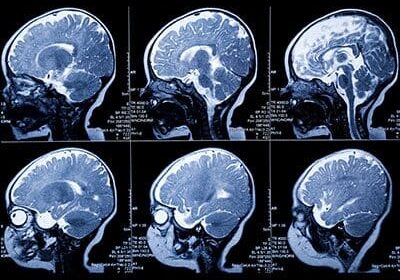

Brain MRI scans showing multiple cross-sections.

MRI Links Neighborhood Disadvantage to Neurodevelopment